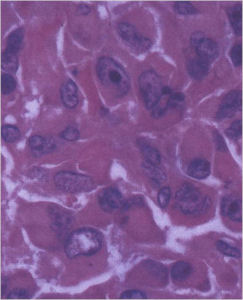

Aggressive Osteoblastoma

- Aggressive osteoblastoma is a distinct rare type of osteoblastoma that has a much more aggressive local behavior than a conventional osteoblastoma. They have a higher chance for local recurrence after removal.

- There has been controversy about the true existence of this type of tumor and whether these tumors are actually low grade osteosarcomas.

- They have a similar appearance microscopically as a conventional osteoblastoma except the osteoblasts are twice as large and have an epithelioid quality with abundant eosinophilic cytoplasm (Epithelioid Osteoblasts).

- Aggressive osteoblastoma is a borderline lesion lesion between osteoblastoma and osteosarcoma. It is not a precursor to osteosarcoma. It does not metastasize.

- Aggressive osteoblastomas usually occur in an older age group than conventional osteoblastoma.

- Most patients are older than age 30. It affects a broad variety of bones.

- Aggressive osteoblastomas are usually larger than a conventional osteoblastoma and have been reported to be up to 8.5 cm in diameter.